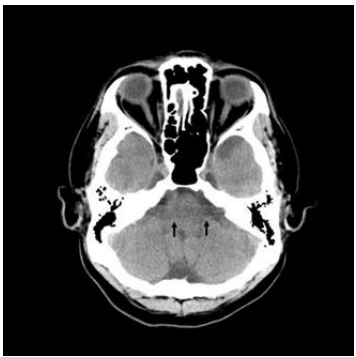

31. 下圖電腦斷層影像中,箭號所示條紋狀較暗區域為何種假影?

(A)ring artifacts (B)metal artifacts (C)motion artifacts (D)beam-hardening artifacts